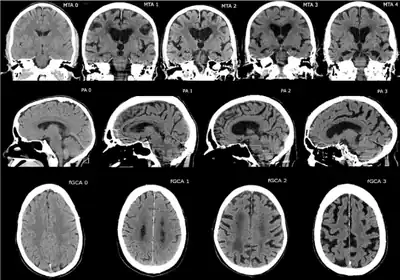

CT and MRI are most commonly used to observe the brain for cerebral atrophy. A CT scan takes cross sectional images of the brain using X-rays, while an MRI uses a magnetic field. With both measures, multiple images can be compared to see if there is a loss in brain volume over time.[20]